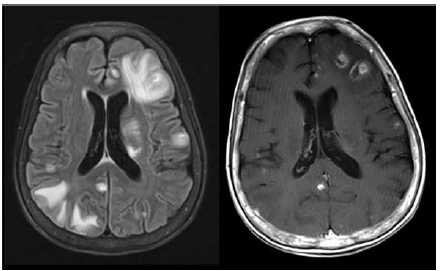

Paciente do sexo masculino, 48 anos, com quadro de confusão mental há 7 dias. Tem antecedente de HIV há 18 anos, com interrupção do tratamento por conta própria há 3 anos. Ao exame, está desorientado e desatento. Realizou a ressonância magnética de crânio mostrada a seguir. O líquor tem 7 células (linfomononuclear) com bioquímica normal e tinta da China negativa.

Enunciado 3568881-1

A principal hipótese diagnóstica é: